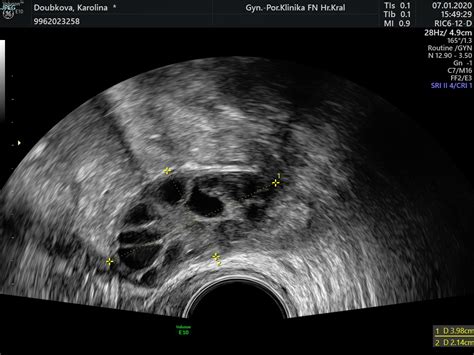

- Polycystické vaječníky (PCO): Stav charakterizovaný výskytom viacerých malých cýst na vaječníkoch, spojený s hormonálnymi nerovnováhami.

- Ultrazvukové vyšetrenie: Transvaginálny ultrazvuk je kľúčový na vizualizáciu vaječníkov, maternice a na identifikáciu gestačného vaku alebo cýst. Lekár dokáže zhodnotiť veľkosť, tvar, umiestnenie a štruktúru útvarov.